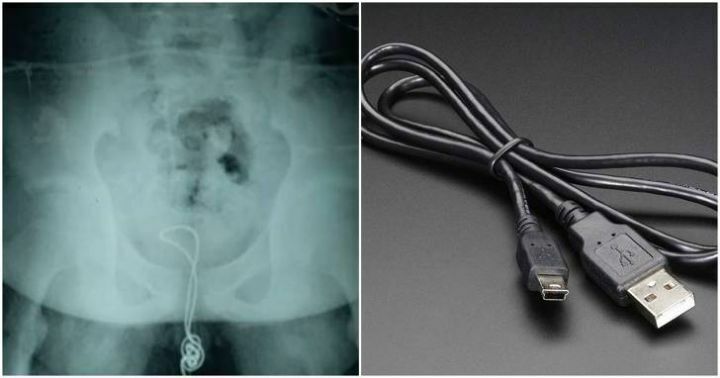

요도자위의 최후.jpg

요도에 뭐 쑤셔넣는 자위하다가

패혈증와서 콩팥 한쪽 제거 수술하는데

사경을 헤매는중